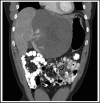

The majority of giant hepatic cavernous hemangiomas are asymptomatic and can safely be observed. However, when a lesion becomes symptomatic, affecting quality of life or cannot be distinguished from a malignancy, then operative therapy should be considered. We herein present a case of a symptomatic 12cm × 14cm × 17cm "mega" hemangioma (>10cm) of the left hepatic lobe. This lesion was initially refractory to transarterial embolization of the left hepatic artery, but was subsequently treated successfully with a left lateral extended hepatic segmentectomy (resection). We thus advocate a rational treatment algorithm for management of hepatic "mega" hemangiomas.